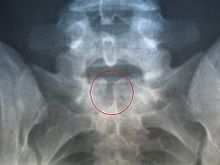

Appel désespéré pour sauver le petit « Boughlita Djad » Mon bébé, né le 02/10/2012 à l’hôpital de Skikda, est atteint trois lourdes pathologies, à savoir : - La Spina-bifida. - Microphtalmie bilatérale. - Malformation génitale (pénis collé aux testicules). Avant la naissance de mon bébé, j’ignorais l’existence de ces maladies et aujourd’hui je suis complètement perdu. Dieu sait que je ne veut pas perdre mon enfant, c’est pourquoi que je lance cet appel désespéré à toutes les âmes charitables pour m’aider dans le combat que je dois mener pour sauver mon petit « Djad » dont le dossier médical est ci-joint. Voici mes coordonnées : Boughlita Salim Adresse : Cité Mohamed Namous, maison boughlita n° 13 Skikda Algérie. Tél/Mobile : (213) 05 55 02 97 51